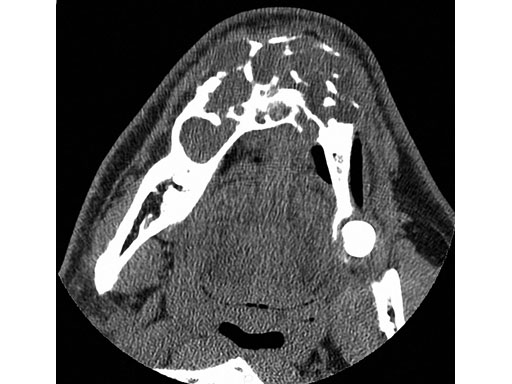

Case 1: A 47-year-old man transferred to the authors hospital approximately 10 days following the resection of a large, benign, locally aggressive odontogenic tumor of the mandible. He was primarily reconstructed with a locking reconstruction plate. The plate dehisced and the patient was unable to eat or swallow leading to his emergent admission to the authors hospital for reconstruction of his mandible with a composite vascularized flap (fibula). The initial internal hardware was removed and a 2.5 mm matrix mandible locking reconstruction plate contoured and applied to the remaining mandibular rami to aid in the reconstruction of the subtotal mandibular defect.

Fig 2 Preoperative situation.

Fig 3 ab Initial plate from lateral and submental vertex views.

Fig 7ab Postoperative 3-D CT scans from lateral and submental vertex views.